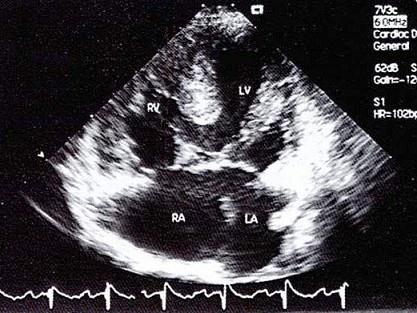

该病例最可能的诊断?(?)A.原发孔房间隔缺损B.左室右房通道C.心内膜垫缺损D.继发孔型房间隔缺损E.混合型房缺

选项 A.原发孔房间隔缺损 B.左室右房通道 C.心内膜垫缺损 D.继发孔型房间隔缺损 E.混合型房缺

答案 C